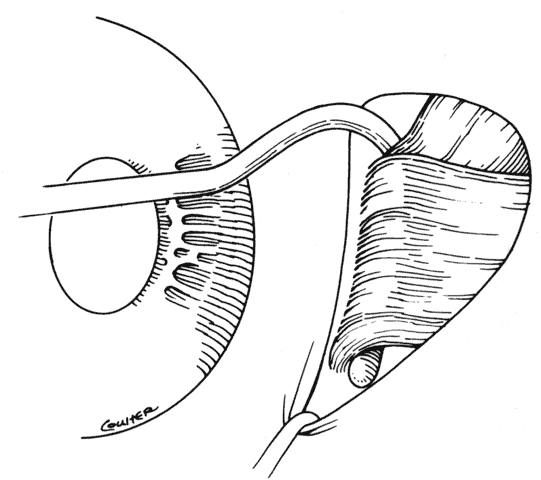

The anesthetic level should provide the patient sufficient comfort. The new rapid-acting intravenous sedation agents provide the surgeon with sufficient sedation to perform some procedures with topical or perimuscular anesthesia. This provides an opportunity for patient cooperation for intraoperative suture adjustment. Once the anesthetic has been administered, the surgeon can proceed with forced duction testing (Fig. 11). If the patient is under general anesthesia or a retrobulbar block has been used, the globe can be moved back and forth and then released to seek its natural position of rest. The “spring back balance test,” popularized by Jampolsky, Scott and Rosenbaum, provides the surgeon with information on the extent and location of restriction (Fig. 12). Forced ductions should include torsional forced ductions to determine if the oblique muscles are restricted.35 During forced ductions, the surgeon should observe the conjunctiva for underlying restrictive tissue bands. Adhesions between these bands and the conjunctiva will cause the conjunctiva to pucker.

Fig. 11. Forced ductions are used to determine the presence and extent of restrictive forces on the globe. This photograph illustrates difficulty abducting the globe due to an inelastic medial rectus muscle resulting from previous resection of the medial rectus muscle.

Fig. 12. The spring back balance test may be performed at any time during surgery. A. The globe is moved from right to left several times and is then released. B. Restrictive bands, scar tissue, or contraction of an inelastic muscle will cause the globe to return to the position induced by the restriction.